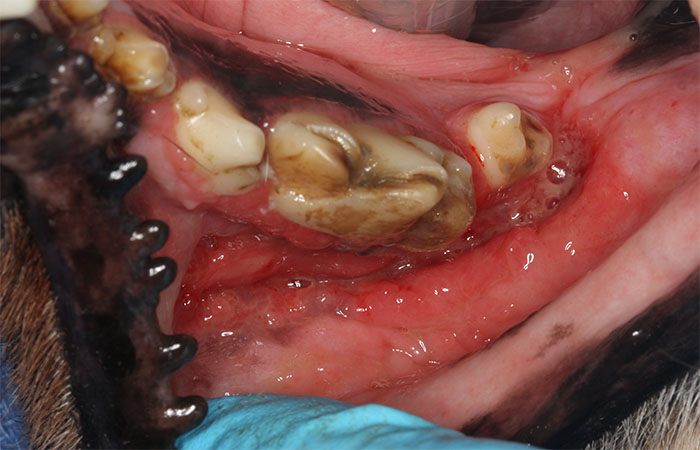

Stomatitis is a generalized term that refers to inflammation of the mouth. However, this painful condition is caused by specific diseases that affect both cats and dogs, and it can be devastating to you and your pet. The term stomatitis in cats refers to feline chronic gingivostomatitis. In dogs, the disease is commonly called canine plaque-reactive stomatitis, or chronic ulcerative paradental stomatitis (CUPS). In both cases, there is an underlying immune-related disorder that results in inflamed and painful surfaces of the cheeks, tongue, and gums.

FCGS is an autoimmune condition in which the cat’s immune response to the teeth and/or oral bacteria is abnormally strong. This results in inflammation and pain that can range from mild to severe. The inflammation centers on the back of the mouth, as well as around the teeth, lips and tongue. While there may be an underlying viral trigger, the exact cause is still unknown. Rarely, FCGS can be managed by maintaining a very clean mouth (anesthetized cleanings at regular intervals and daily brushing at home). Oftentimes, however, more aggressive intervention is needed to help your cat stay comfortable.